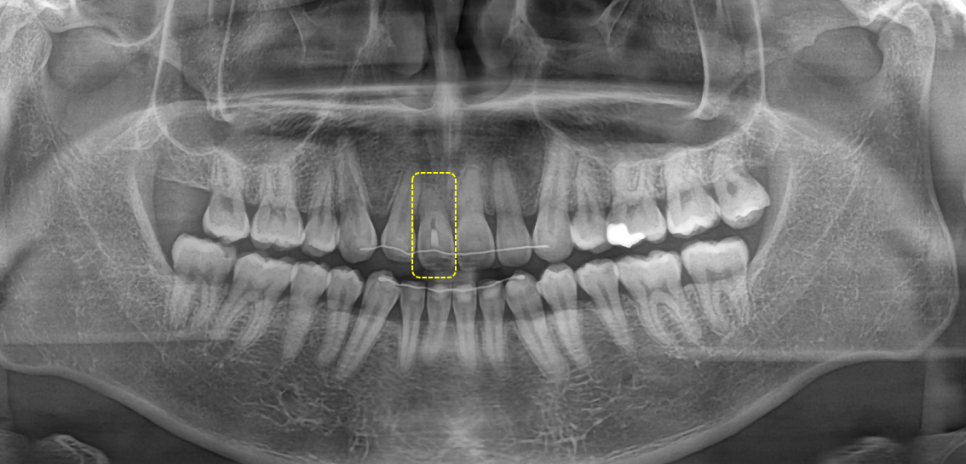

촬영일 : 250905

아주 오래 전에 타치과에서

신경치료를 실패한

경험이 있으셨습니다.

오래된 약재를 제거하고

깨끗하게 비운 신경관을 밀폐한 후

치아 내부에 미백 약제를 넣었어요.

변색 원인이 된 내부 성분을 분해하고

점차 밝은색으로 회복되도록 유도했어요.